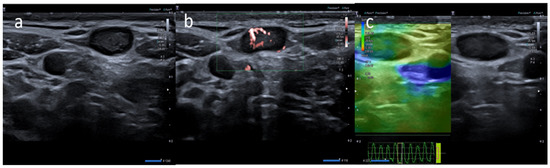

- Cocco, G.; Pizzi, A.D.; Fabiani, S.; Cocco, N.; Boccatonda, A.; Frisone, A.; Scarano, A.; Schiavone, C. Lymphadenopathy after the Anti-COVID-19 Vaccine: Multiparametric Ultrasound Findings. Biology 2021, 10, 652. [Google Scholar] [CrossRef] [PubMed]